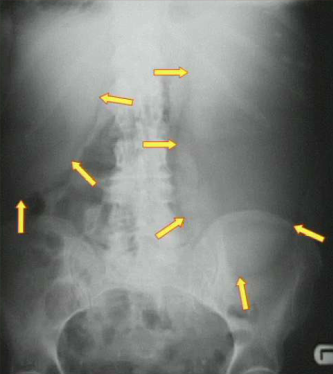

What are the top two causes of this?

1) Adhesions 2) Hernia. Note the dilated loops of bowel indicating small bowel obstruction.